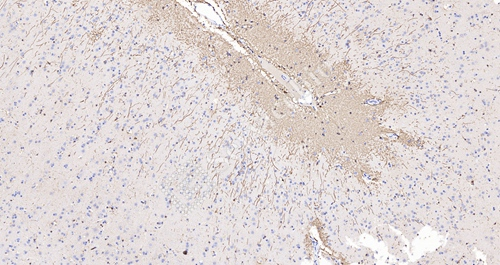

猴脑IHC-GFAP_0.2x

• 阳性定位:细胞质棕黄色颗粒(DAB),细胞核蓝色(苏木素)

• 定量标准:阳性细胞占比>5%且染色强度≥2+(四分级法)

• 背景控制:非特异性染色面积<2%视为合格